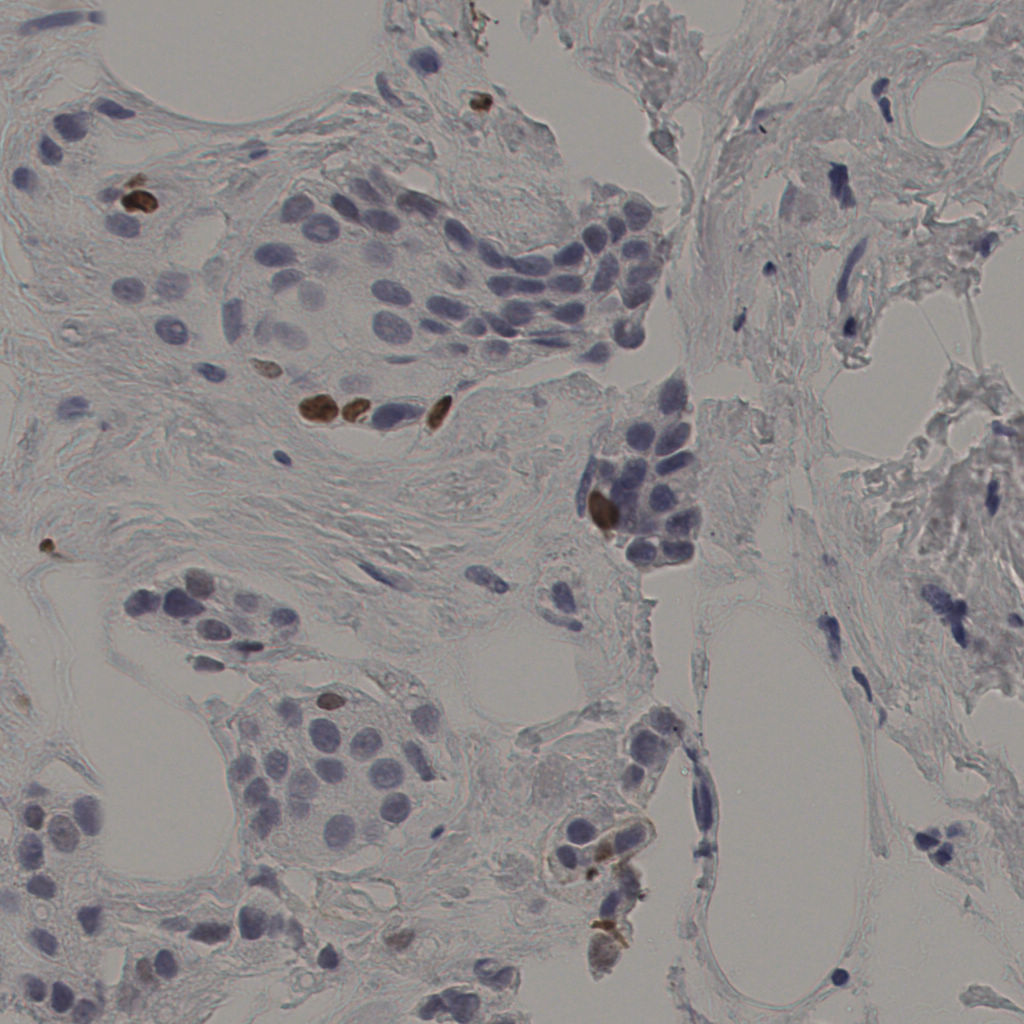

5.31%

Ki67 指数

阴 19502

阳 1093

有效

554

有效率

19%

标记后

标记前